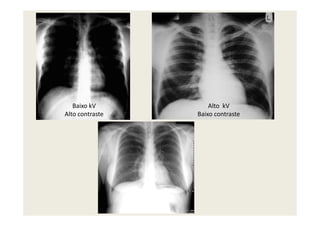

kV ALTO

POUCO CONTRASTE

kV BAIXO

MUITO CONTRASTE

CONTRASTE

BAIXO CONTRASTE

• O excesso de kVp

“atravessa” as estruturas e

imprime o filme sem

permitir diferenciá-las

ALTO CONTRASTE

• O baixo kVp produz feixe

com baixa energia cinética,

incapaz de atravessar o osso

• PRETO E BRANCOpermitir diferenciá-las

• CINZA

• PRETO E BRANCO

KVP E CONTRASTE RADIOGRÁFICO

MÉDIO A ALTO KV

Escala de cinza mais larga

BAIXO CONTRASTE ALTO CONTRASTE

BAIXO KV

Escala de cinza estreita

Tórax

Mama

Degraus mais suaves Degraus mais abruptos